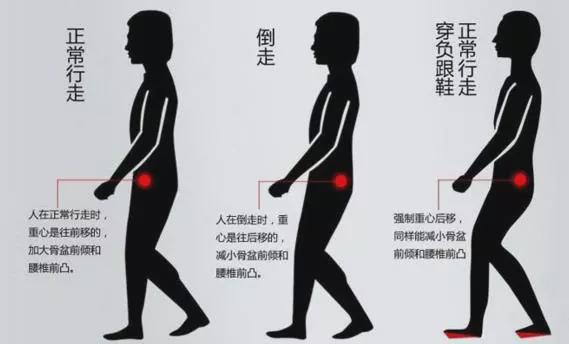

表现为站立或行走时双腿向后弹出,人的重心明显向后倾斜。这是导致步态异常的原因之一。

④倒走训练:患侧伸髋屈膝,支撑患腿时注意防止膝关节过伸;使用护膝或支具防止膝关节过度伸展;协助行走训练时,治疗师用一只手或膝关节协助患膝腘窝,防止行走时膝关节过伸,另一只手协助患侧骨盆上缘,防止行走圈子里。每天进行5至10次训练。